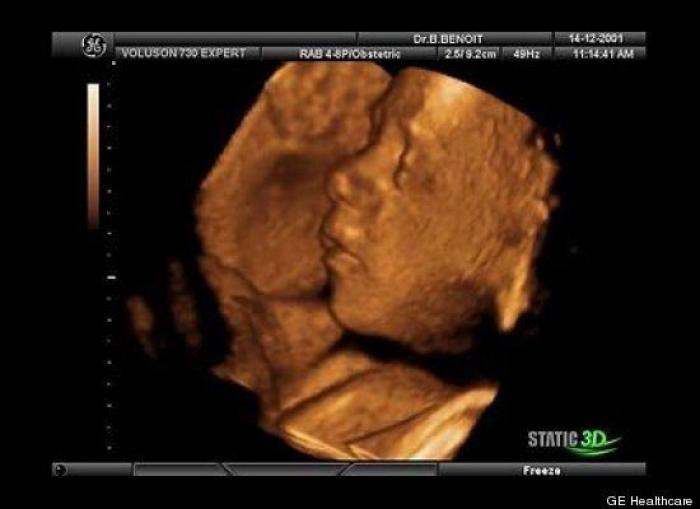

En esta galería puedes ver en fotos como es el desarrollo de un feto de semana en semana:

Desarrollo del feto, en fotos

Ver la galería